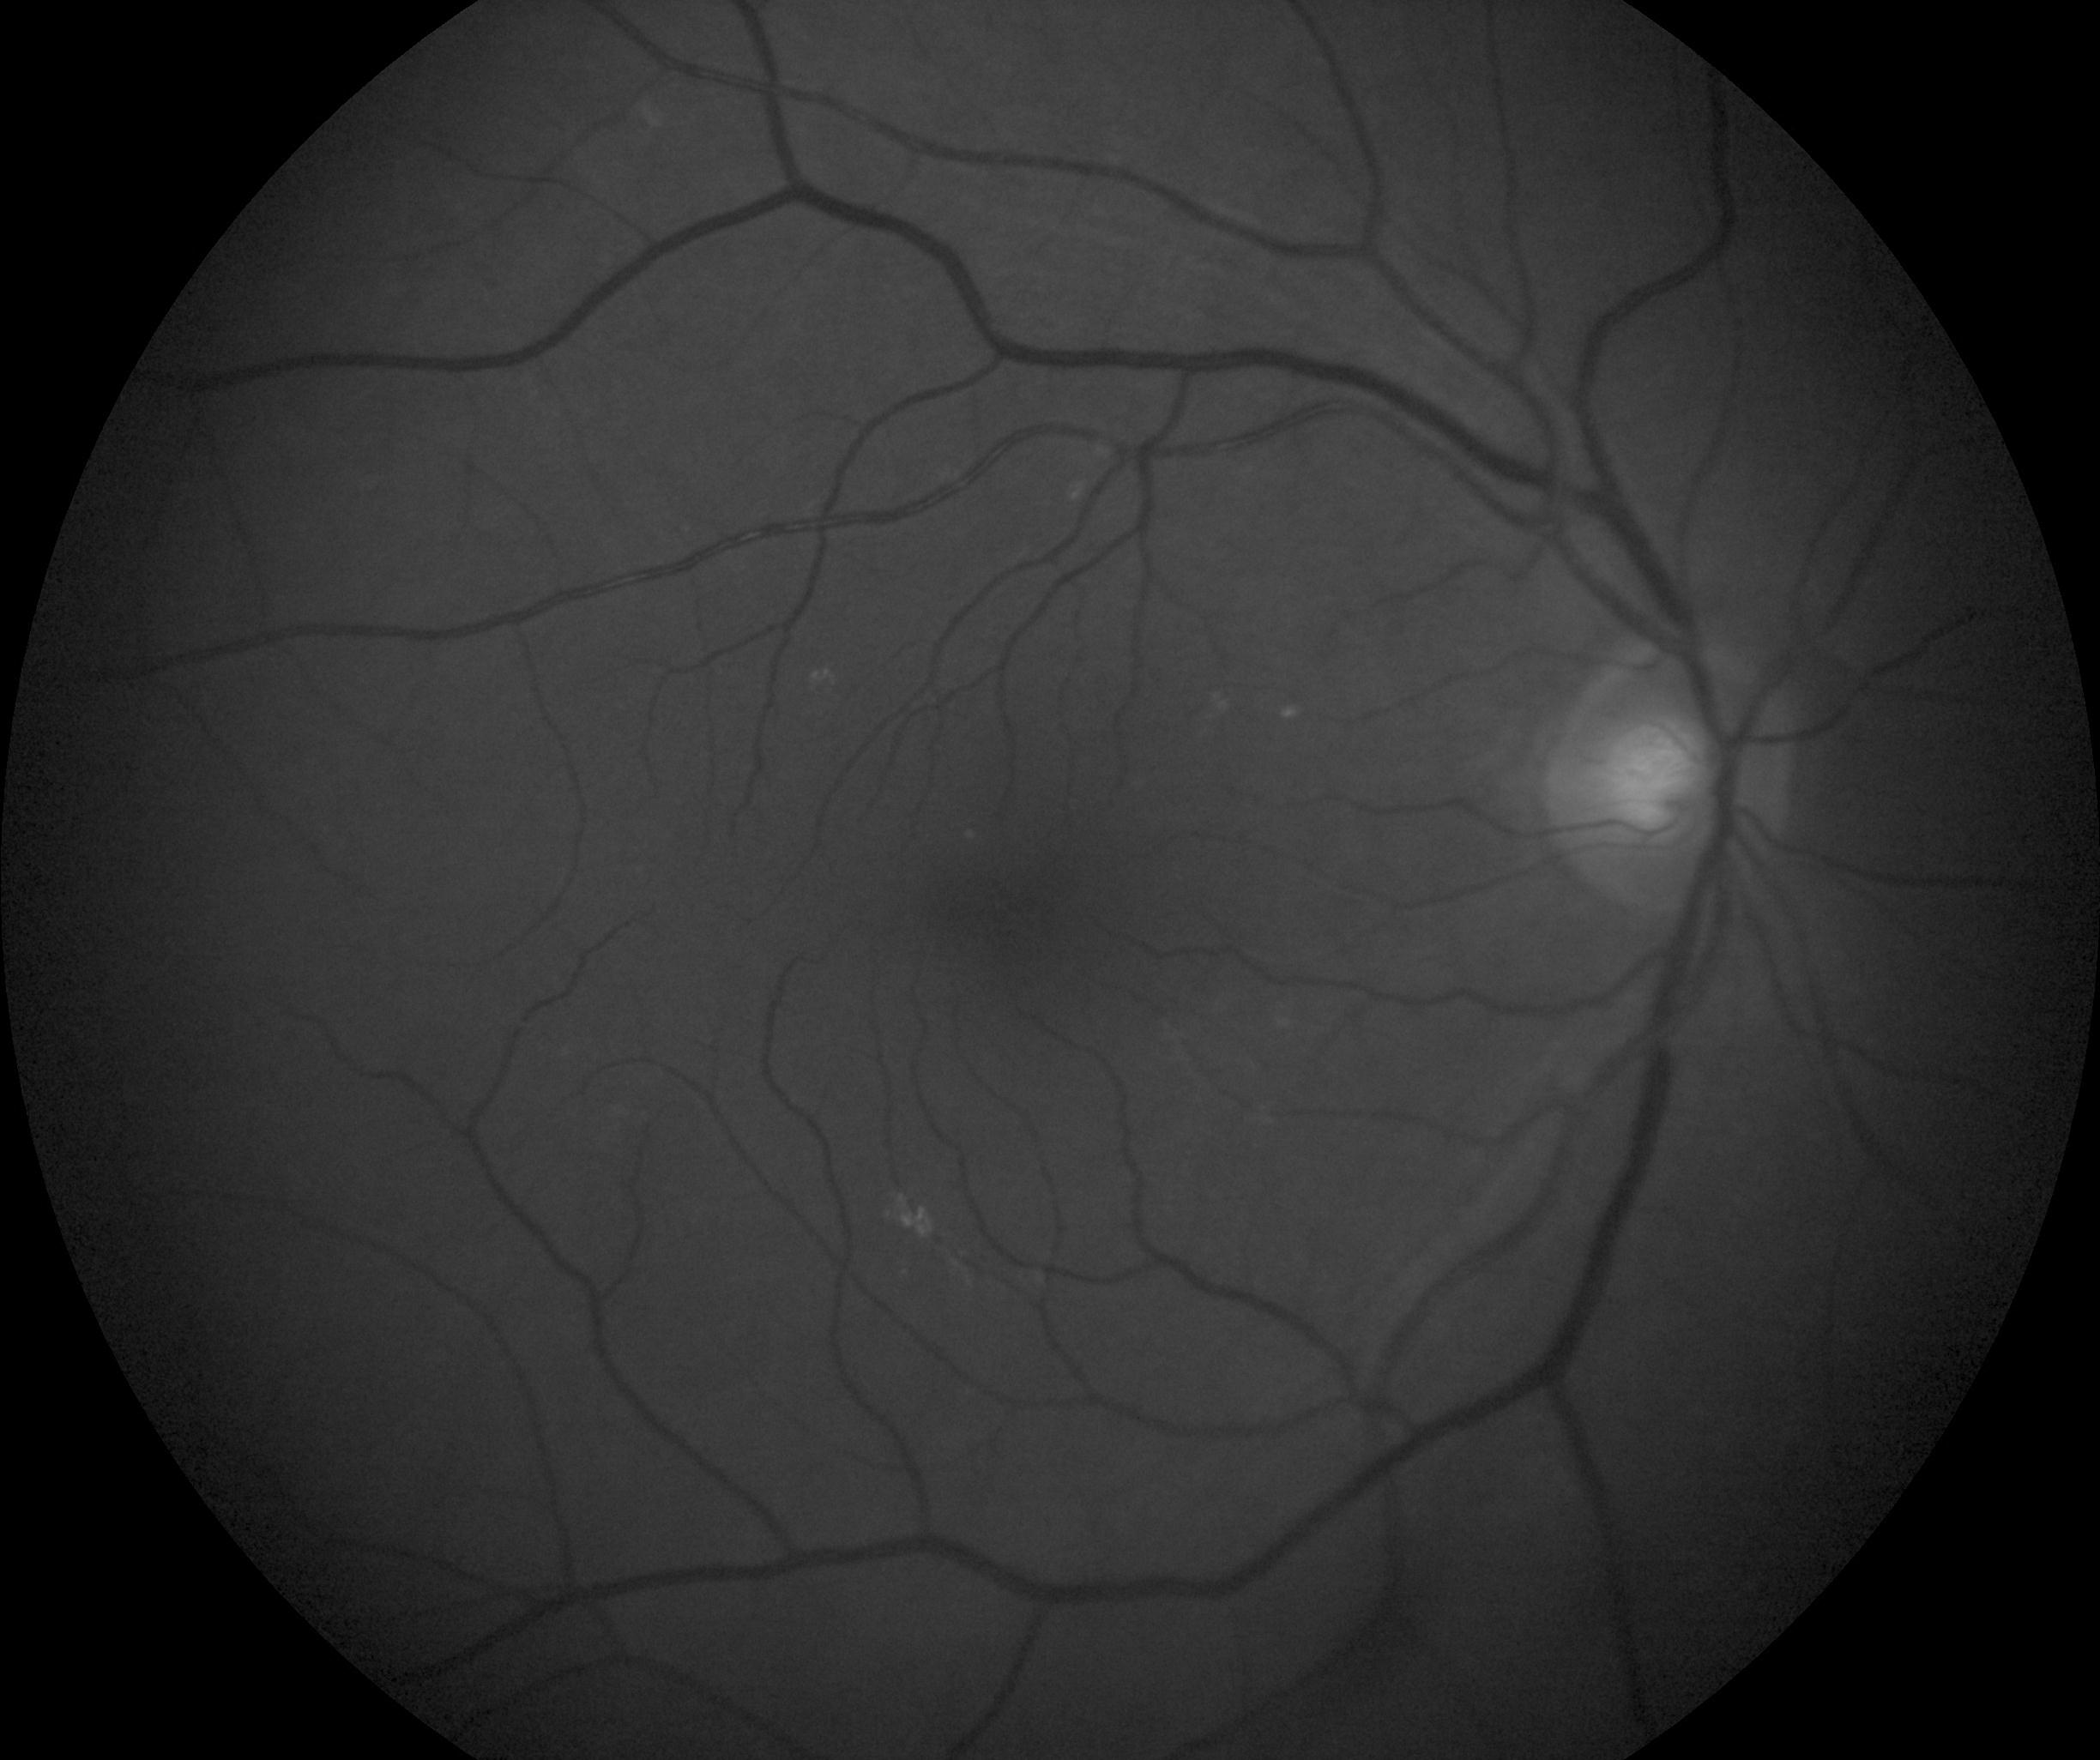

i fotogrammi 1 e 2 sono qualitativamente inferiori o per opacità dei mezzi diottrici (cataratta) o semplicemente perché sfuocati comunque si apprezza la presenza di soft drusen da tenere controllate nel tempo per valutare eventuali evoluzioni e consiglierei le classiche metodiche protettive occhiali con filtri uv in ambienti assolati controllo pressione arteriosa, fattori dietetici, no fumo... senza però allarmare il paziente poiché non vi é motivo.

I fotogrammi 3 e 4 sono sostanzialmente nella norma con qualche hard drusen al polo posteriore.